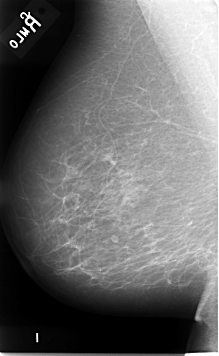

B_3086_1.LEFT_MLO

LEFT_CC LINES 4672 PIXELS_PER_LINE 2736 BITS_PER_PIXEL 12 RESOLUTION 50 OVERLAY

FILE: B_3086_1.LEFT_CC.OVERLAY

TOTAL_ABNORMALITIES 1

ABNORMALITY 1

LESION_TYPE MASS SHAPE OVAL MARGINS ILL_DEFINED

ASSESSMENT 3

SUBTLETY 3

PATHOLOGY MALIGNANT

TOTAL_OUTLINES 1

BOUNDARY